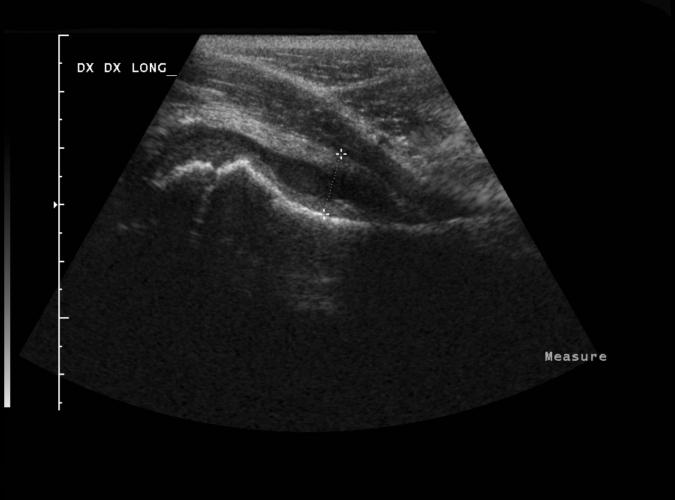

Patologi.

Coxit.

Long, höger höftled.